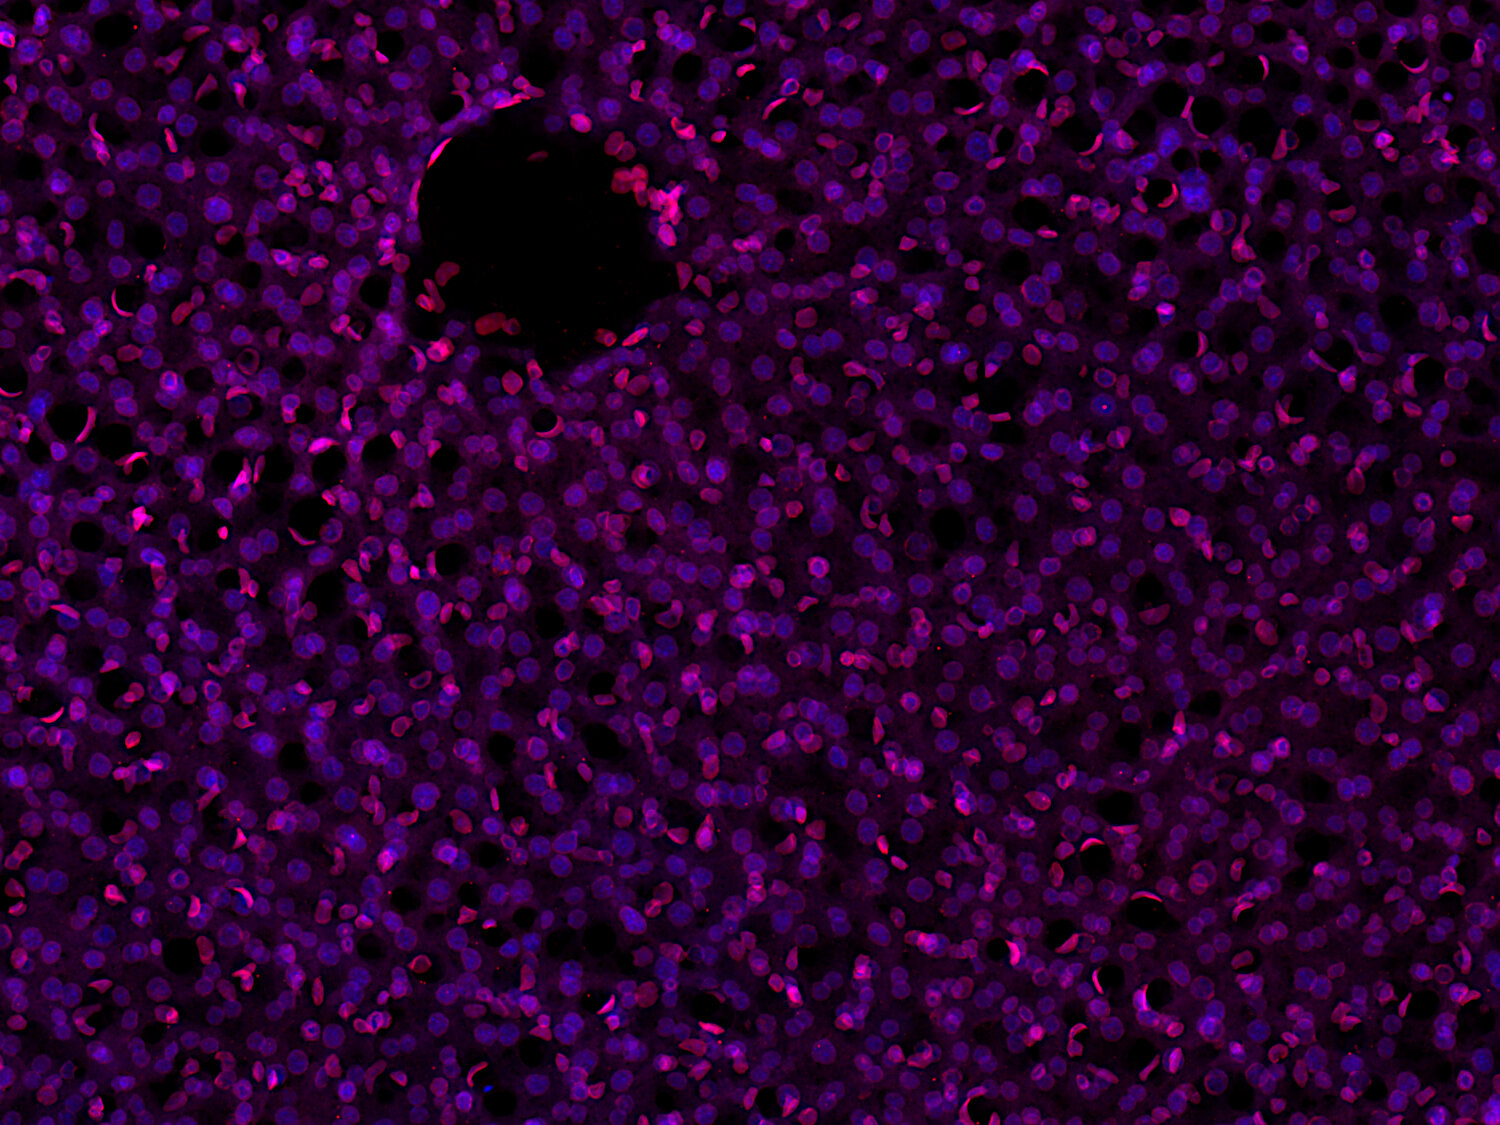

Detection of nuclear Lamin B1 in a formalin fixed paraffin embedded (FFPE) mouse lung section

Lamin B1 (LMNB1) is an intermediate filament-type protein of the nuclear lamina and is ubiquitously expressed throughout development. It plays important roles in many cellular processes like the distribution of heterochromatin and the regulation of gene expression and splicing. The maintenance of LMNB1 protein levels is required for DNA replication and repair and thus mutations in B-type lamins are usually lethal.

Duplication of the LMNB1 gene causes adult-onset autosomal-dominant leukodystrophy (ADLD), a rare neurological disorder in which overexpression of LMNB1 causes progressive central nervous system demyelination. Improper Lamin B1 expression is often present in tumor cells and decreased levels are observed for example in colon cancer, breast cancer and B-cell malignancies. Lamin B1 loss is also a senescence-associated biomarker and distinguishes senescent from proliferating cells in pre-neoplastic lesions or marks senescent cells in various age-related pathologies.